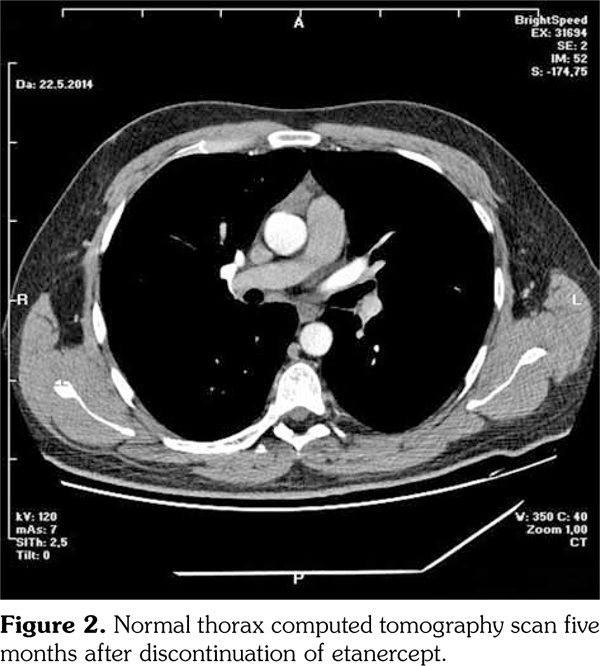

Lymph node biopsy was performed by broncoscopy and endobronchial ultrasonography. Biopsy result was compatible with granulomatous disease. All the infectious studies performed on pulmonary lymph node tissues were negative. Angiotensin converting enzyme level was at the upper limit with a value of 47.6 U/L (normal: 8-52 U/L). Sarcoidosis was found to be compatible with the condition after excluding tuberculosis. Etanercept was ceased following the diagnosis of sarcoidosis. No additional medical treatment was suggested for sarcoidosis. Non- steroid anti-inflammatory drugs were prescribed for the control of AS. Five months later, follow- up thorax computed tomography scan showed resolution of the mediastinal lymphadenopathies (Figure 2).

However, pain, dysfunction in daily living activities related with AS, high disease activity markers (erythrocyte sedimentation rate: 53 mm/hour, C-reactive protein: 40 mg/L [normal: 0-6 mg/L], and Bath Ankylosing Spondylitis Disease Activity Index of 6.3 [normal: 0-4]) during the period without etanercept prompted us to consider another anti-TNF-α agent. At the seventh month of etanercept cessation, golimumab with the dosage of 50 mg/month was commenced to compete with the symptoms and findings associated with AS. At the ninth month of follow-up period after inception of golimumab, the patient had no pain with normal disease activity markers. There were no pathological findings regarding sarcoidosis in the examination of the pulmonary system (Figure 3). A written informed consent was obtained from the patient.